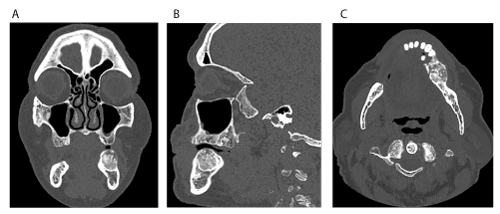

Clinical examination revealed a non-tender, expansile, exophytic intraoral lesion associated with the left edentulous area of the posterior mandible in the first and second molar region (Figure 1). The surface of the lesion was smooth and exhibited no erythema or ulceration. No facial asymmetry or lymphadenopathy was evident. On palpation, the lesion was firm, non-tender, non-compressible, and fixed to the underlying tissues. Prior to surgery, a panoramic radiograph (Figure 2) and a computed tomography (CT) scan (Figure 3) were obtained. The panoramic radiograph demonstrated a well-defined, well-circumscribed, ovoid, and expansile radiolucent/radiopaque lesion with corticated borders in the posterior left body of the mandible. No destruction of adjacent anatomical structures, root resorption of adjacent teeth or involvement of the inferior alveolar canal were evident. On CT, the lesion measured 2.3 x 2.1 x 2.0 cm and appeared to have an intact cortex with a sclerotic periphery and evidence of internal ossification. The lesion did not appear to be associated with the proximate premolars. The differential diagnosis included benign fibro-osseous lesions (i.e. ossifying fibroma, cemento-osseous dysplasia) and osteosarcoma with a high preference for ossifying fibroma.

Figure 3. Computed tomography (CT) imaging. (A) Coronal view. (B) Sagittal view. (C) Axial view. Note the sclerotic periphery, evidence of internal ossification and benign appearance